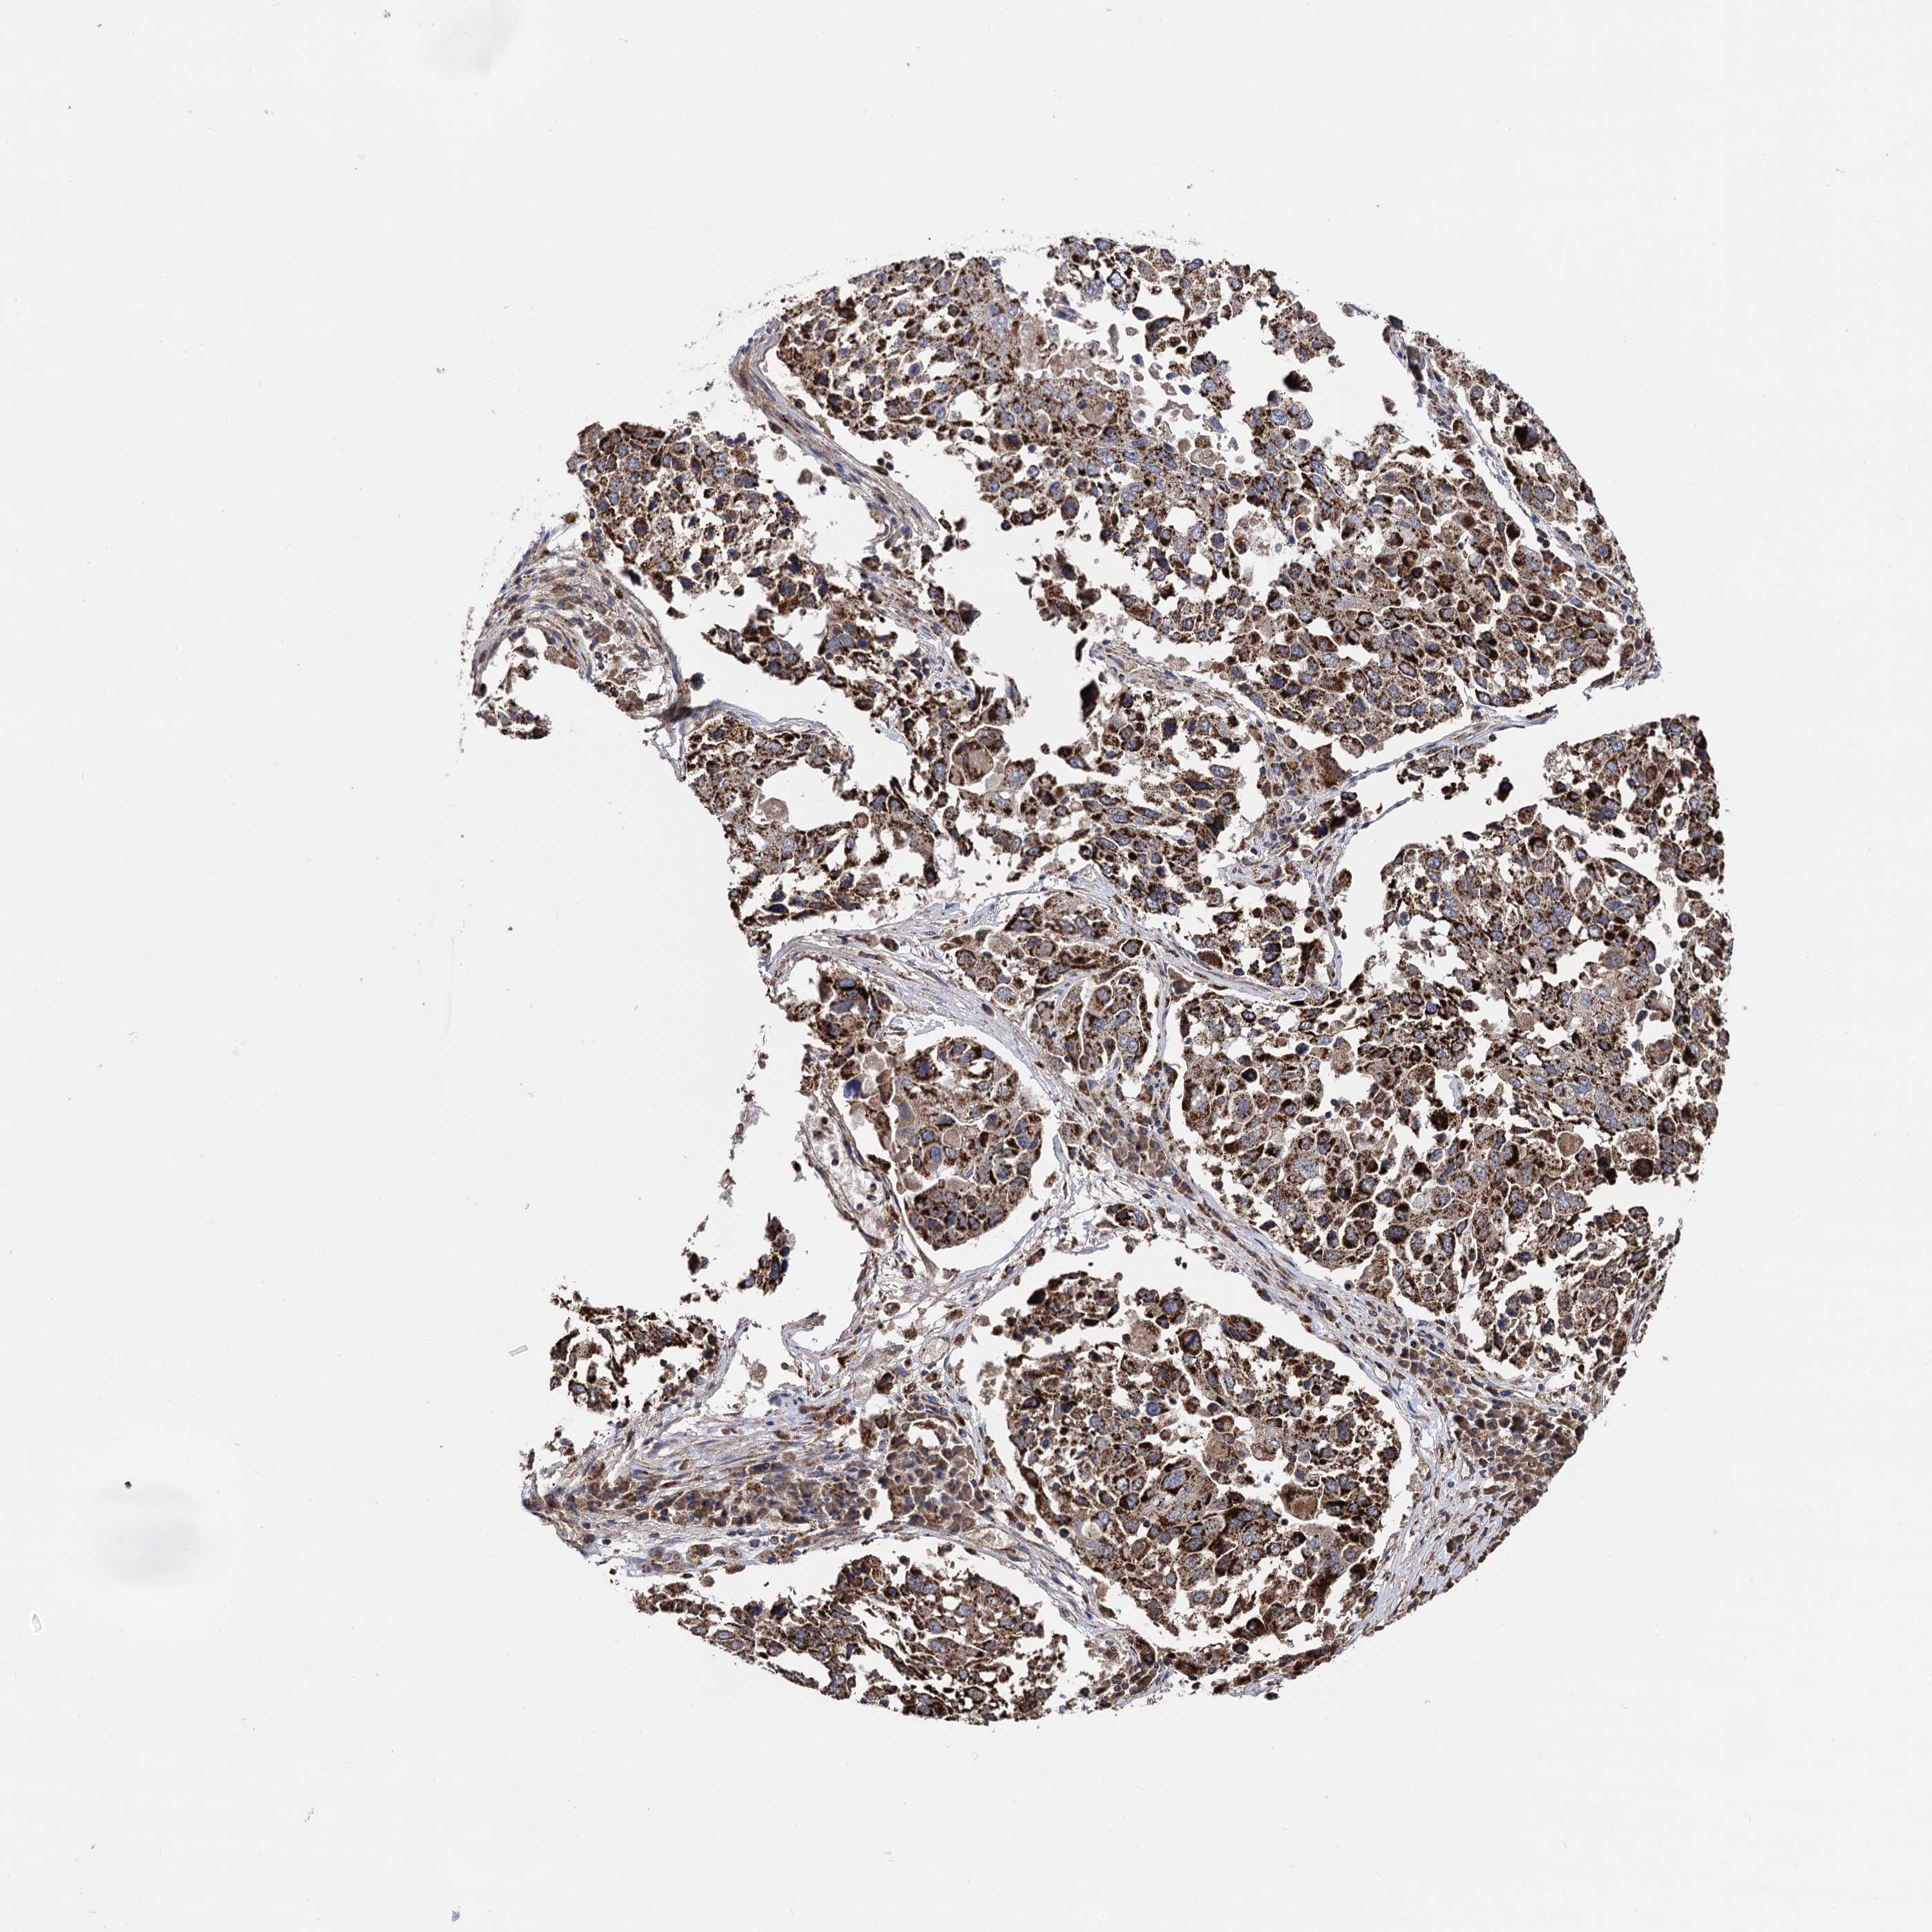

CANCER LUNG CANCER Show tissue menu

Lung cancer

Human cancer